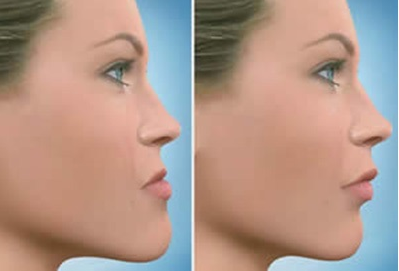

・横顔(Eライン)で「口元が出てる」ように見える

・3D顔面スキャン+セファロ分析で骨格的なズレを可視化

・笑顔・横顔・話すときの表情を動的に記録し、「口元の出方」と「印象の違和感」の関係性を把握

・患者のゴール(フェミニン/シャープ/ナチュラルなど)に合わせて、“印象ゴール”から逆算する矯正計画